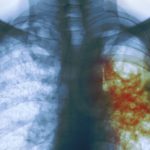

Infographics: Interesting Facts About Tuberculosis

Facts About Tuberculosis